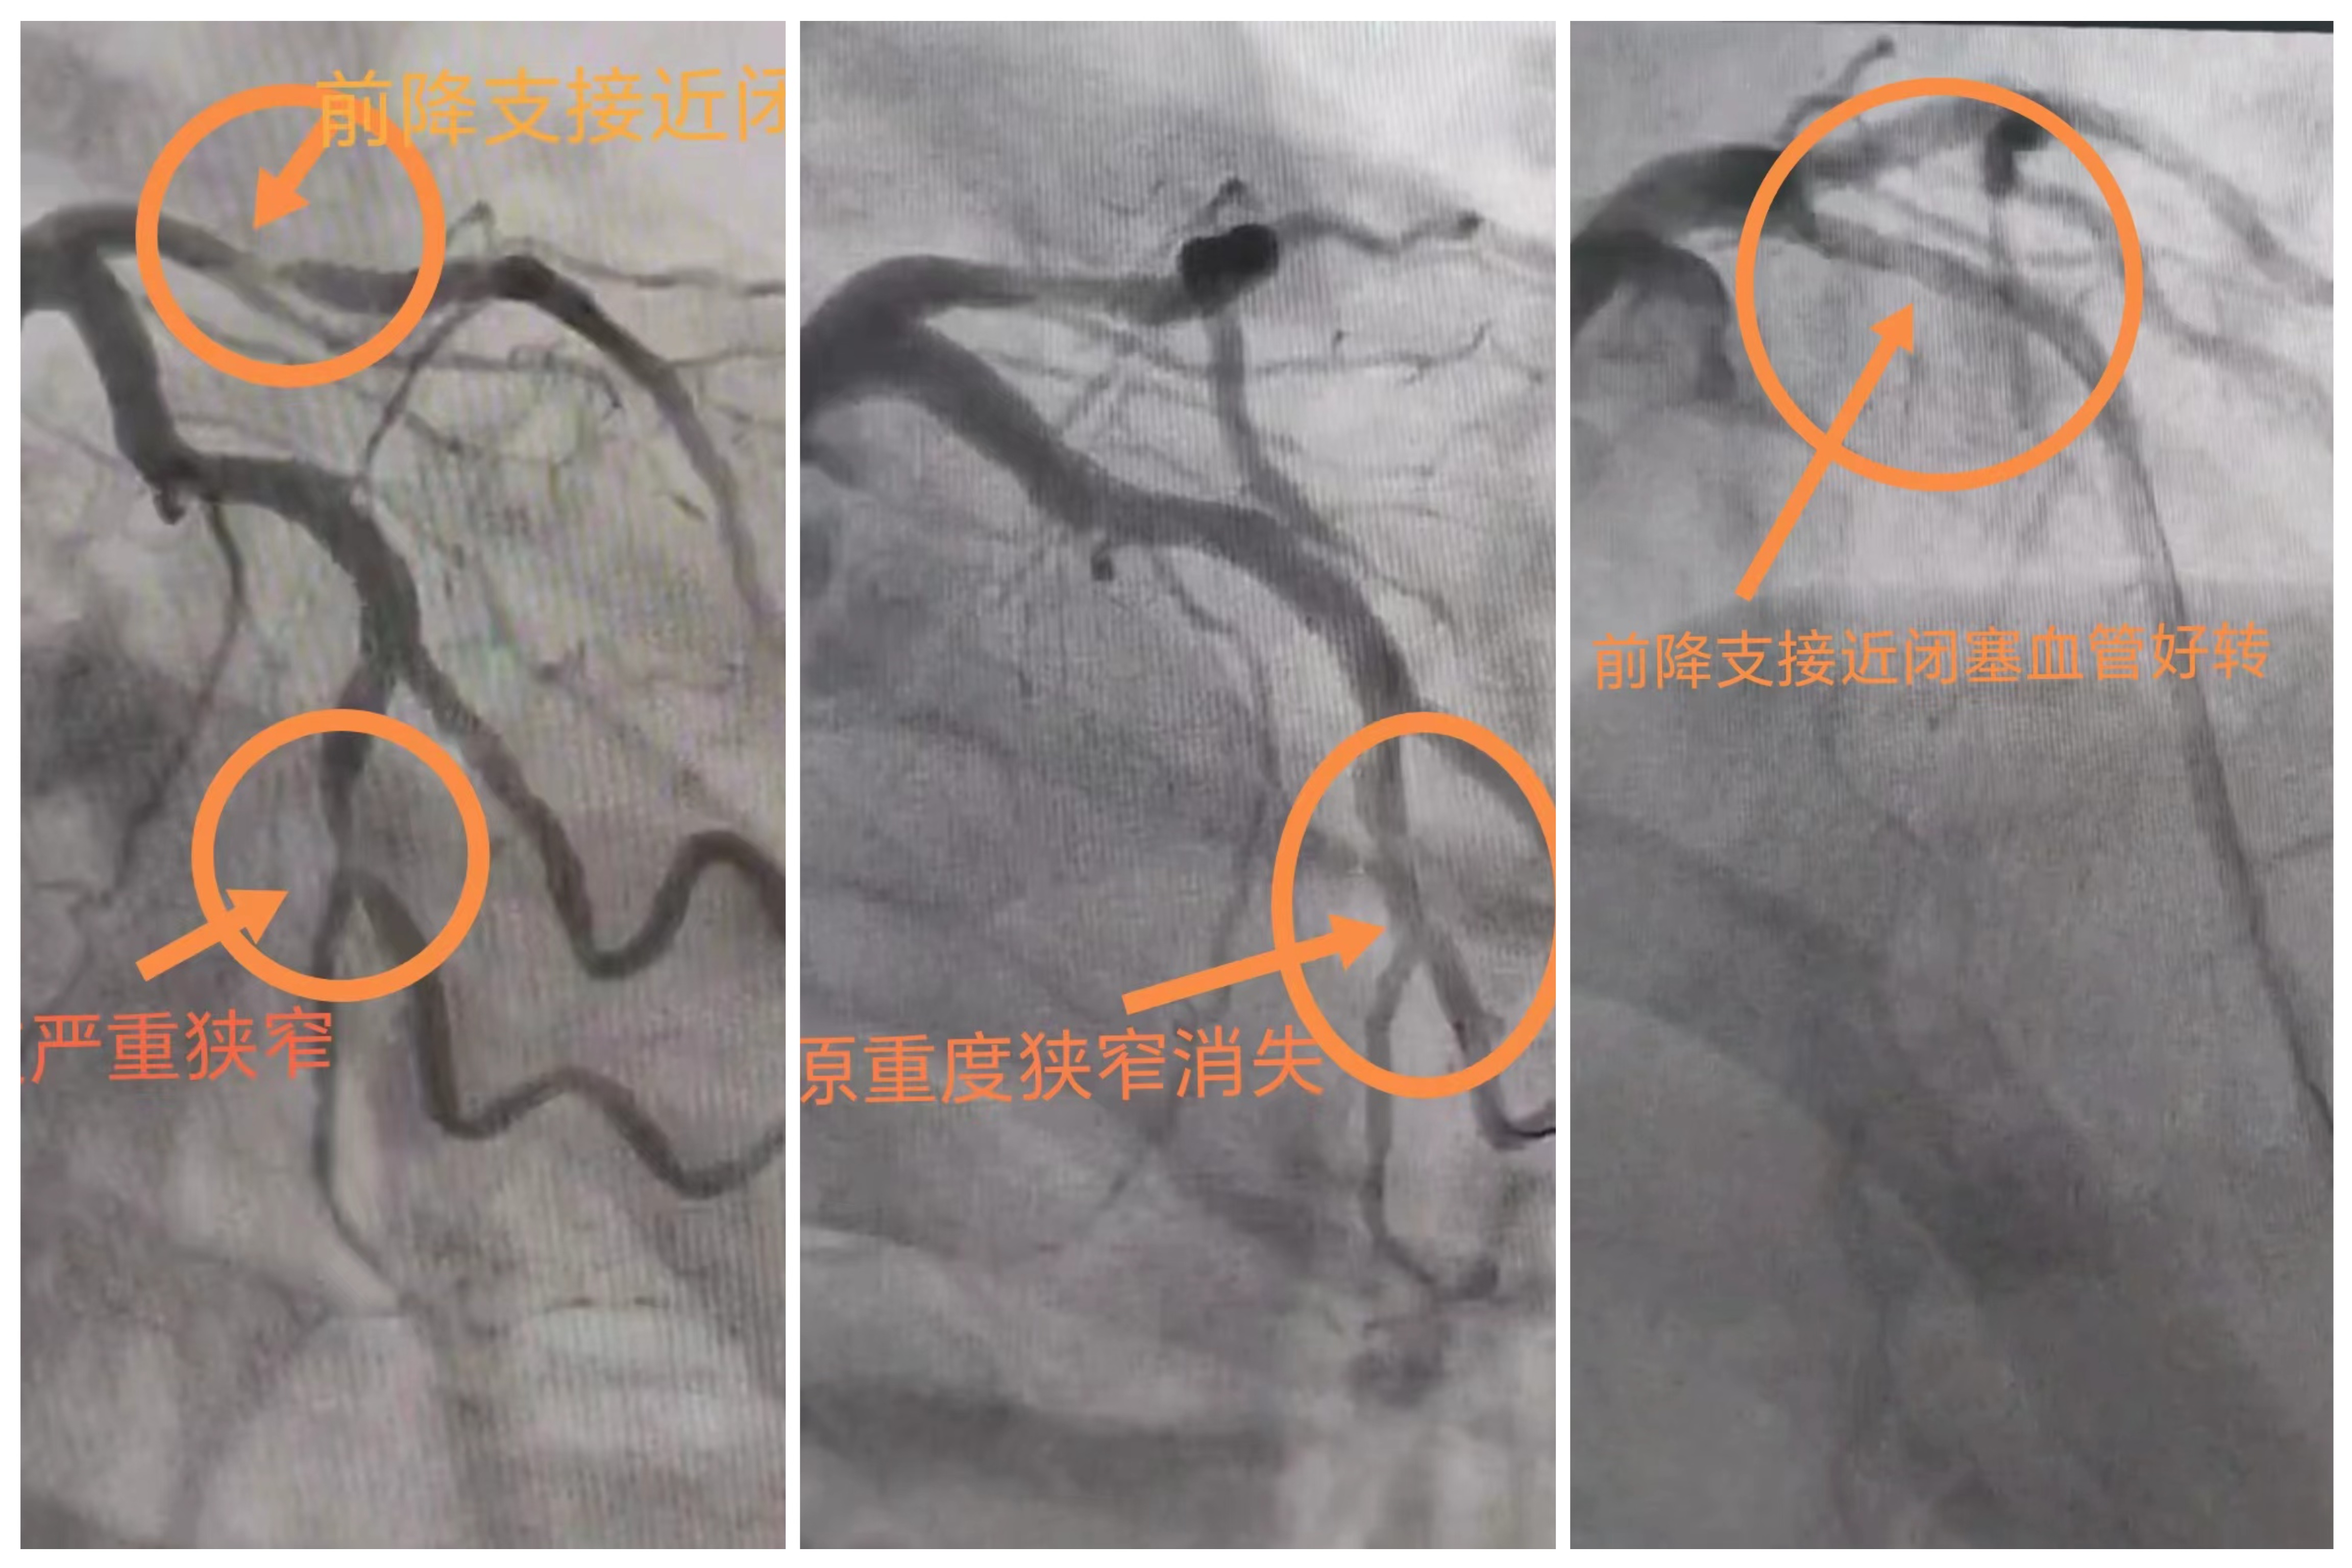

一例急性心肌梗死患者术前术后造影图

心脏的缺血坏死会导致致命心律失常、心衰、休克甚至猝死的发生,因此,早期有效识别心梗及尽早施救至关重要。冠脉造影是诊断急性心肌梗死金标准,尽早开通闭塞血管可以挽救病危生命。